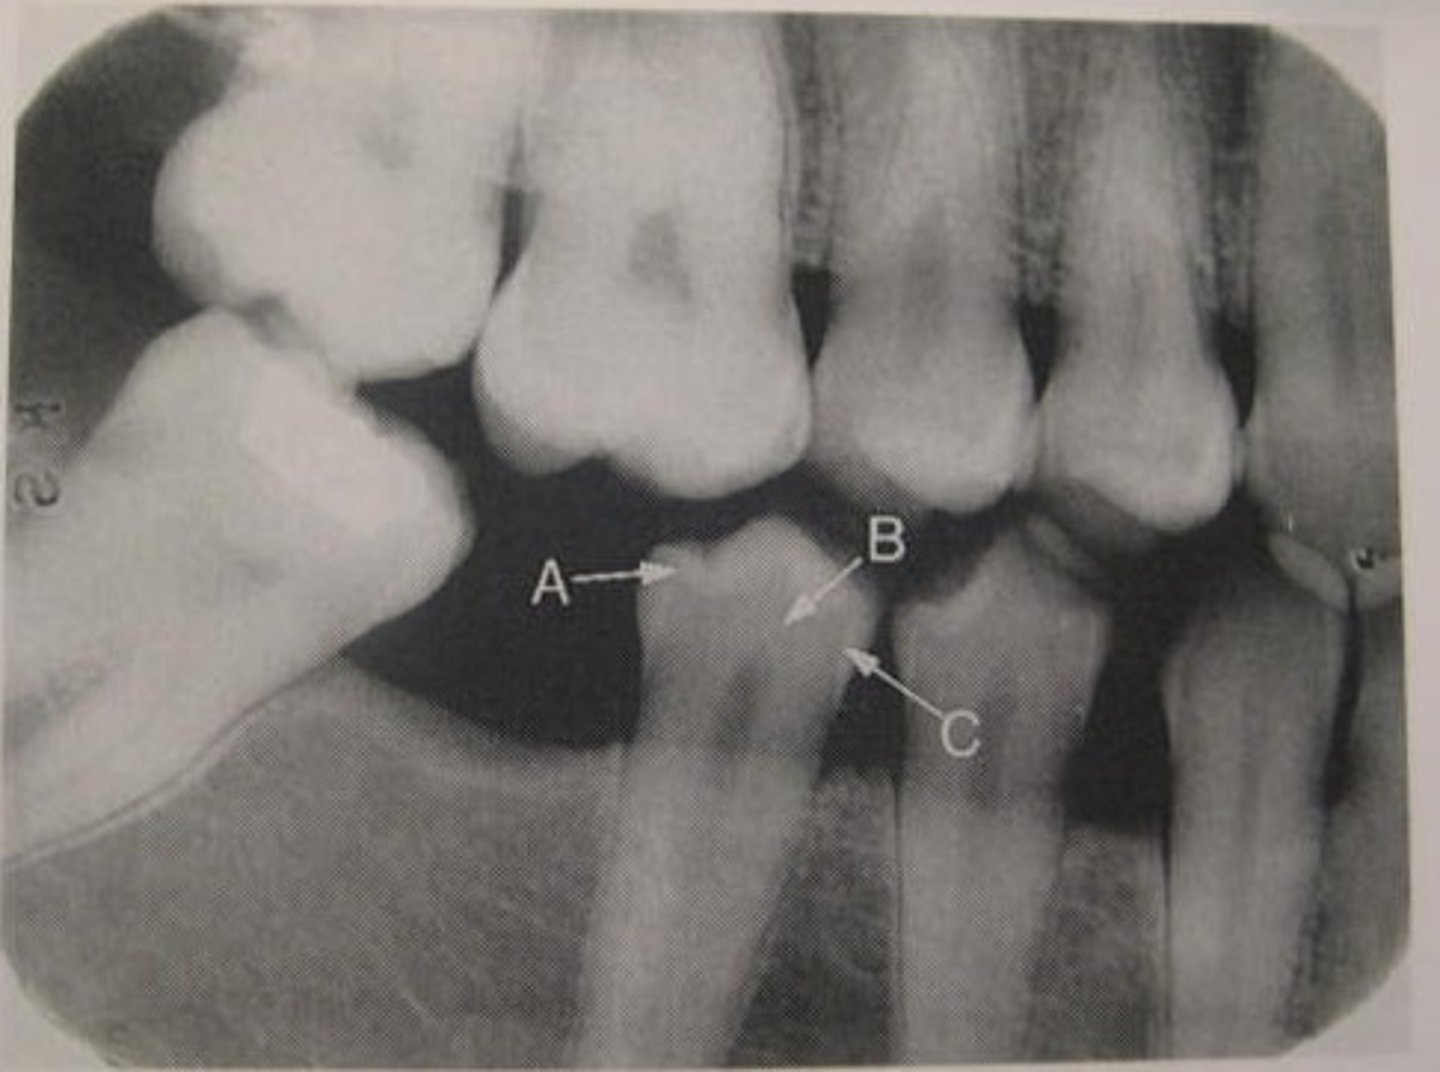

What kind of bone is shown here?

Cancellous bone

Enamel

What is arrow A pointing to?

Dentin

What arrow B pointing to?

Pulp cavity

What is the radiolucent structure shown here?

Dentino-enamel junction (DEJ)

What arrow C pointing to?

Lamina dura